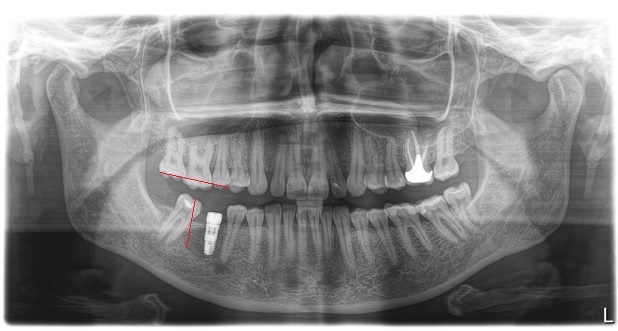

Был установлен имплантат и параллельно начато лечение у ортодонта. Как мы видим, нижний правый 7-ой зуб наклонен, а верхний правый 6-ой несколько выдвинулся вниз.

Обратите внимание, необязательно устанавливать полноценную брекет систему для того, чтобы устранить эту проблему. Достаточно приклеить 3 брекета на 4-й, 5-й, и 7-ой зубы, и при помощи специальной пружины толкать проблемный зуб на свое место. На верхней челюсти ситуация несколько иная. Для устранения проблемы устанавливаются два ортодонтических винта. Один со стороны щеки, а второй со стороны неба. К зубам клеятся две кнопки, и дается тяга (специальные резинки). Они-то и «тянут» зуб на место.